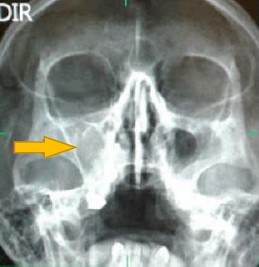

A análise da imagem permite fazer várias observações anatômicas.

Disponível em: https://dicasradiologia.blogspot.com/2016/03/como-identificar-sinusite-na-radiografia-raiox.html, acesso dia 13/11/23.

Avalie a sentenças a seguir.

I. A sinusite é uma inflamação da mucosa dos seios paranasais ou mais conhecidos com seios da face, localizado na região frontal da cabeça é formada por cavidades ósseas ao redor do nariz, maçãs do rosto e olhos.

II. O nome mais utilizado para esse problema é rinossinusite, pois o processo inflamatório atinge tanto a mucosa dos seios da face como a mucosa nasal.

III. A sinusite é uma das inflamações comuns nas estações outono e inverno, devido à presença dos principais vírus e bactérias que causam gripes e resfriados e,consequentemente, a coriza e as secreções.

É correto o que se afirma em